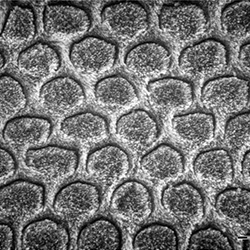

Per facilitare la spiegazione, vi lasciamo qui di seguito le immagini della struttura del tessuto più forte che abbiamo nel corpo umano: lo smalto. Essendo una delle strutture più difficili, è proprio quella che ha bisogno di un protocollo di incisione ad acido per ottenere la demineralizzazione e quindi l'adesione.

Quando si applica l'incisione totale acida sulla dentina, la parte inorganica viene rimossa, demineralizzandola, lasciando un aspetto simile a una rete, anche se si potessero osservare ancora i tubuli dentinali. In questo modo rimane solo la materia organica composta da collagene, che non è influenzata dall'acido ortofosforico. Nelle seguenti immagini si possono vedere le strutture prima e dopo l'applicazione dell'acido.

Evidentemente dobbiamo eseguire l'incollaggio della dentina umida. Nel caso della dentina secca, i tubuli dentinali si vedono su una superficie più o meno omogenea, tuttavia le fibre di collagene non sono chiaramente osservate. Al contrario, nella dentina umida si può vedere una superficie a rilievo più grande dove i tubuli dentinali sono più visibili grazie alle fibre di collagene.